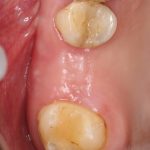

Рекомендации по установке имплантов. Для всех. Часть V.